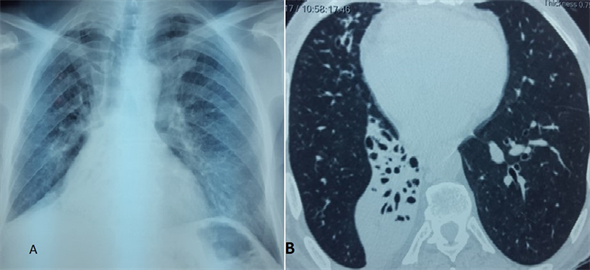

Mr H. F, is a 61 year old patient, having as antecedent a tuberculosis ganglionnaire in childhood for more than 3 years, he has had a productive cough with muco-purulent sputum, aggravated by the occurrence of repetitive haemoptysis of low abundance. The clinical examination at its admission found asymmetry of the rib cage by retraction at the expense of the right hemithorax. The chest x-ray showed right basi-thoracic areolar images with retraction of the trachea towards the right side and ascension of the right diaphragmatic dome (Figure 1(A)). The thoracic CT scan revealed a lower right lobar systemic parenchymal parenchymatous focus, in which there are dilated bronchi of the cylindrical type (Figure 1(B)). The search for AFB in sputum was negative. Bronchial fibroscopy showed muco-purulent sputum in the middle lobar and right lower lobar bronchus without visualization of fistula. As part of the preoperative assessment, spirometry had shown a FEV1 of 1.92 L, or 57% of the theoretical. Transthoracic echocardiography was without abnormality. It was decided then, a lower right lobectomy. Right posterolateral thoracotomy was found to have dilated the right lower lobe bronchi in relation to calcified subcarinal adenopathy fistulated in the right lower lobe bronchus, with inflammatory magma enclosing the fistula-free esophagus of the latter. The gesture consisted of a regulated resection of the right lower lobe as well as the carenal adenopathies. The postoperative course was without particularity. The anatomopathological results of the excision specimen did not indicate tuberculosis. The mean follow-up of the patient was 3 years, with no complications.

Figure 1. (A) chest radiograph showing right hemithorax retraction and tracheal retraction to the right side; (B) CT thoracic in parenchymatous window and axial cut showing a focus of parenchymatous condensation systemized lobar lower right, in which are lesions of dilations of the bronchi of the cylindrical type.